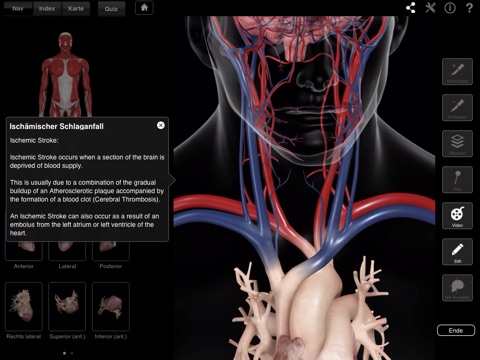

Diese App ist hauptsächlich als Lernmittel gedacht, durch ihre Index-Funktion kann sie jedoch auch als schnelles und innovatives Nachschlagewerk verwendet werden. Der Anwender kann einzelne Elemente auswählen, die dann in der App automatisch vergrößert und beschriftet werden.

Zusätzlich ist diese App ideal für Ärzte, Lehrer und Fachkräfte. Sie ermöglicht ihnen, ihren Patienten und Studenten detaillierte Ansichten des Herzens und/oder Animationen zu zeigen - um die Herzfunktion, Erkrankungen und Verletzungen erklären zu können.